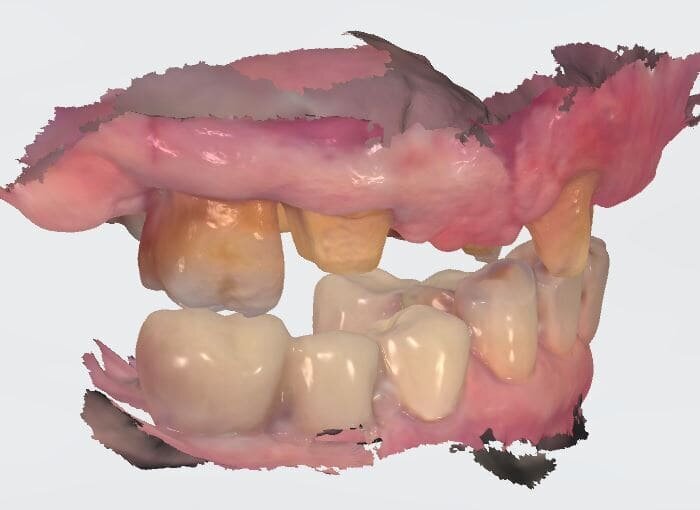

L’informazione diagnostica dettagliata è fornita dalla CBCT, pertanto abbiamo pianificato la sua esecuzione dopo la prima provvisorizzazione dell’arcata superiore evitando lo scattering da metalli presenti. Il file STL del wax-up (Fig. 6) associato al file STL dell’impronta senza provvisorio (Fig. 7) e al file DICOM radiologico (Figg. 8, 9) ha permesso una corretta progettazione chirurgico implantare (Fig. 10) nel rispetto della porzione ossea della cresta residua, ottimizzando la conseguente realizzazione della dima chirurgica (Fig. 11) per il posizionamento degli impianti in sede 1.2 e 2.2 (Figg. 12-14) anche nel rispetto della posizione degli elementi in antagonismo (Fig. 15). Il primo provvisorio avrà diverse funzioni tra cui la valutazione dell’inclinazione coronale, l’ingombro volumetrico e il supporto labiale del gruppo frontale per la correzione dell’emergenza del labbro superiore (Fig. 16). Dopo un breve periodo di stabilizzazione funzionale di almeno due mesi, si valutano i movimenti mandibolari, masticatori, il ripristino dei tessuti parodontali e il condizionamento biologico degli elementi intermedi. Nello specifico del caso trattato abbiamo evidenziato subito un collasso della masticazione associato a un morso profondo che non avrebbe consentito alcuna protesizzazione degli elementi mancanti (Fig. 2). Pertanto abbiamo dovuto realizzare un rialzo di masticazione anche per correggere l’emergenza degli elementi sostitutivi. La preparazione degli elementi residui concepita ha eliminato tutti i materiali che avrebbero creato un disturbo nell’indagine radiologica (Fig. 17).

I dati raccolti sono molti ma la procedura digitale consente di sommarli e confrontarli senza limiti e indicando le possibili migliori e correzioni lungo il percorso. Dopo un breve periodo di condizionamento dei tessuti (Fig. 30) rileviamo l’impronta master per la finalizzazione ultima della riabilitazione protesica. L’impronta degli elementi naturali viene rilevata posizionando dei fili detrattori secondo la tecnica del doppio filo mentre per gli impianti verranno usati gli scan body dedicati (Fig. 31). Le potenzialità digitali consentiranno di avere una stabile lettura della posizione di centrica rilevandola prima della rimozione dei provvisori e sovrapponendola a provvisori rimossi (Fig. 32). In laboratorio l’odontotecnico realizza i modelli (Figg. 33, 34) sovrappone le immagini (Fig. 35) e raccoglie gli elaborati dei vari passaggi che porteranno alla finalizzazione del progetto digitale (Figg. 36, 37). Gli impianti in Zirconia non offrono molte soluzioni protesiche, è importante che il loro posizionamento tenga conto di quest’aspetto mettendo l’odontotecnico nelle condizioni più favorevoli (Fig. 38). Questa sistematica prevede l’uso di un moncone in titanio cementato nella struttura protesica che permette l’avvitamento all’interno dell’impianto. Nella connessione implantare è presente un’intercapedine dove alloggia il collarino in titanio del T-base totalmente inglobato all’interno della zirconia, evitando comunicazioni coi tessuti adiacenti. Va comunque considerato l’aspetto tecnico importante legato allo spessore della struttura in zirconia che deve avvolgere l’intero moncone in titanio. (Fig. 39, 40).

Fig. 35_Sovrapposizione di un’immagine stilizzata degli elementi realizzabili con un margine muso ricreato.

Fig. 36_Wax-up digitale funzionalizzato per entrambe le arcate in visione frontale.

Fig. 37_La medesima immagine viene sottratta dagli elementi di supporto. Tale visione consente di evidenziare i margini coronali, di valutare i movimenti masticatori, gli svincoli coronali le conformazioni anatomiche ottimizzando le singole funzioni.